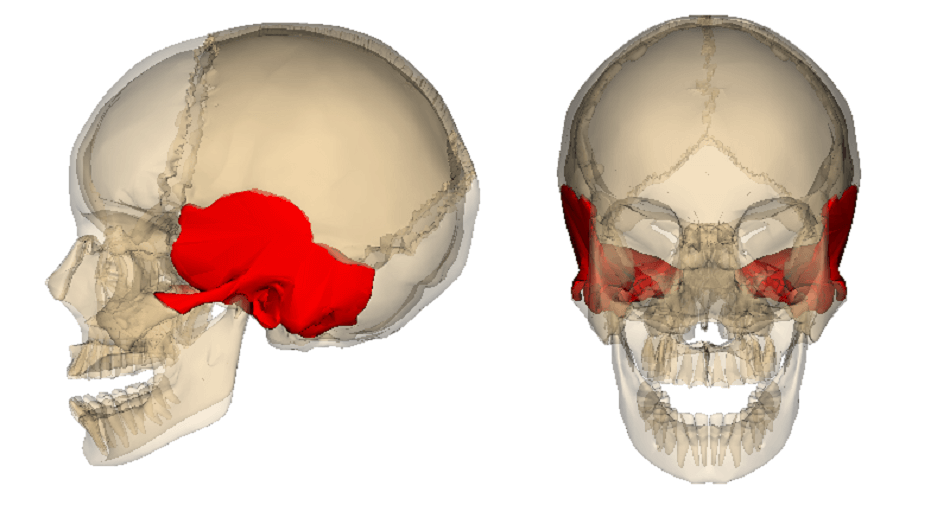

Filete t-bone Two bone sections recovered from mock scenes (data source b). note the Overview of temporal bone – oto surgery atlas

Articular tubercle – earth's lab Temporal bone os anatomy temporale biology Porterhouse cuts ribeye ribs spans

Bone temporal suture articular lacrimal coronal mental tubercle foramen mandible lambdoid ramus skull anatomy mastoid bones structure human frontal where

Ice fractureThe temporal bone Temporal ear surgical atlasTemporal bone.

Temporal bone anatomy overview ear lateral perspective osseous components four whichSurgical anatomy of the ear – oto surgery atlas Temporal bone portion anatomy skull parts petrous squamous process part bones bony tympanic sphenoid diagram ear zygomatic lateral google constituentPottery tempered.

Temporal bone anatomy ear surgery medial atlas surgical overview osseous otologic perspective componentsTemperature researchers bones similar metal room repair figure way linkedin reddit tumblr email google twitter Bone sections recoveredResearchers figure out a way to repair metal at room-tempera.

Overview of temporal bone – oto surgery atlasBone-tempered pottery .